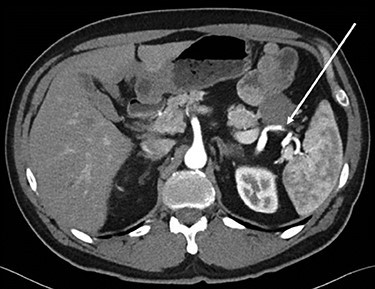

Abdominopelvic CT scan disclosed a 3.7-cm mass, between the tail of the pancreas and the splenic hilum, causing a narrowing of the splenic vein and splenomegaly (Figs 1–3).

Axial CT scan of abdomen, selected image from a pancreatic protocol. Early arterial phase during which there is opacification of the arterial structure (arrow).